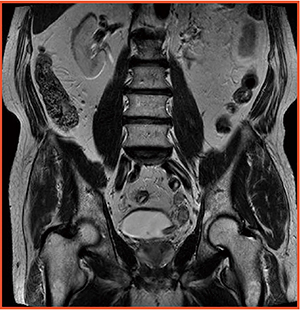

図3 Female Pelvis:卵巣腫瘍

RF照射の均一性を実現。T1WI,T2WIはもちろんDWIも明瞭に描出され,

3TのSNRを生かした画像と言える。

(画像提供:岩手医科大学附属病院)